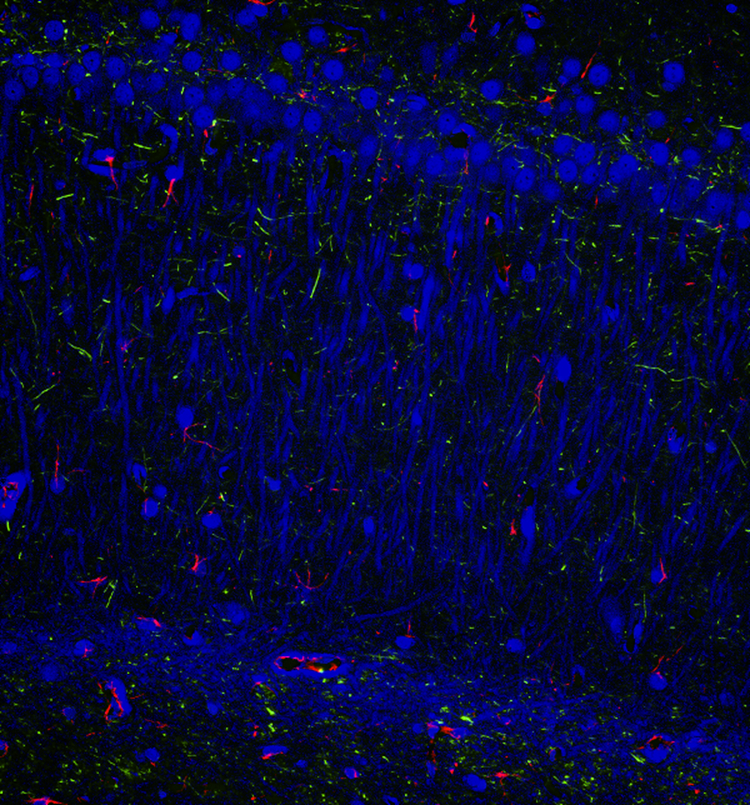

04 宽光谱,拓展红外成像边界

DP75采用可切换的IR滤镜设计,让它的光谱响应轻松触达1000nm。从此,无论是可见荧光成像,还是不可见的CY7染色记录,都仅需一台DP75来完成。